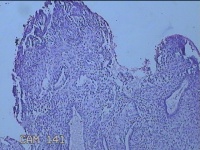

宫腔内容物

性别

女

年龄

47岁

临床诊断

1.异常子宫出血 2.慢性宫颈炎

一般病史

不规则阴道流血21天。

标本名称

大体所见

灰白暗红色不规则碎组织2.5x1.8x0.3cm一堆。

图1